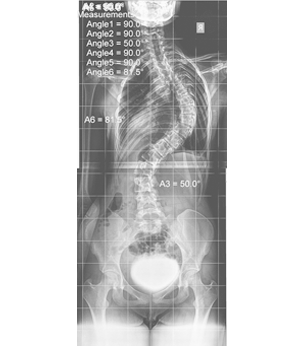

Σκολιώσεις από 40° – 60°

Οι σκολιώσεις μετά τις 40° διορθώνονται πιο δύσκολα γιατί η σκολίωση και οι παραμορφώσεις της έχουν περάσει στους σπονδύλους, δημιουργώντας αυτό που ονομάζουμε πλαστική παραμόρφωση. Αυτό σημαίνει ότι η θεραπεία πρέπει να είναι πιο έντονη και πιο μακροχρόνια.

Τα αποτελέσματά μας είναι πολύ καλά μειώνοντας την γωνία τουλάχιστον στο μισό της αρχικής.

Παιδιά όπως αυτό στο παράδειγμα, που η γωνία έφτασε στις 120⁰ επειδή δεν ήθελε σε μικρή ηλικία να φορέσει κάποιο κηδεμόνα.